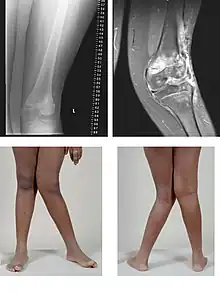

A very severe case of genu valgum of the left knee following bone cancer treatment

Genu valgum, commonly called "knock-knee", is a condition in which the knees angle in and touch each other when the legs are straightened.[1] Individuals with severe valgus deformities are typically unable to touch their feet together while simultaneously straightening the legs. The term originates from the Latin genu, 'knee', and valgus which means "bent outwards", but is also used to describe the distal portion of the knee joint which bends outwards and thus the proximal portion seems to be bent inwards.